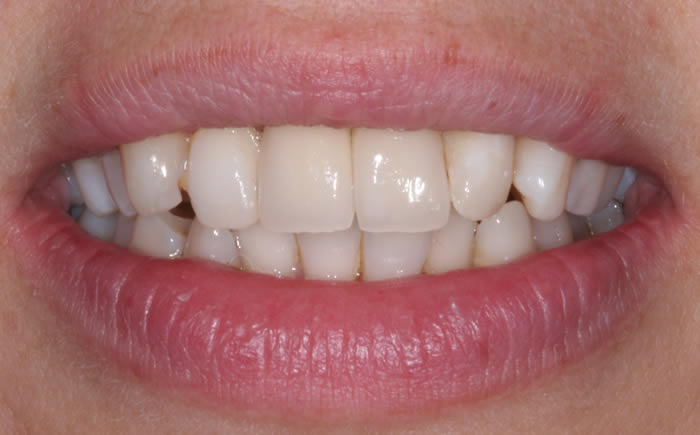

More front teeth replaced by dental implants

Case Three (4 images)